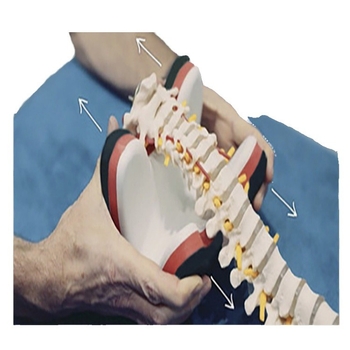

A Badu nem vállal felelősséget a vásárlásért Nyaktartó masszázspárna húzási és ortozissal – XMG modell 445345, polietilén anyag, doboz 60, egészségügyi masszázs Ettől: Egészségügyi Eszközök Kiegészítői Ha az nem a megrendelőlapon keresztül történt.